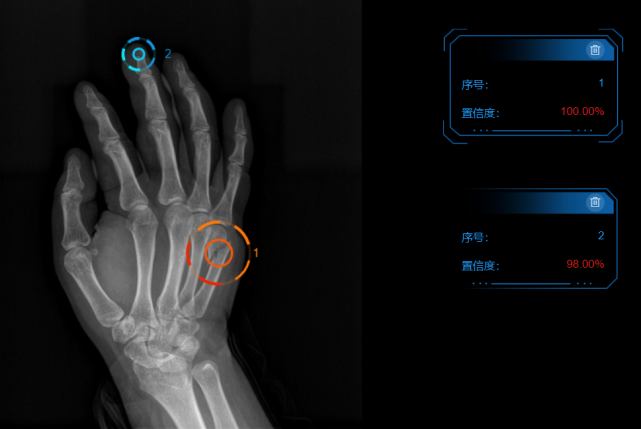

李爱银向“医学界”介绍,患者拍完DR片后,人工智能软件会直接在后台出具一份报告,将所有怀疑骨折的部位全部标红,这一过程用时低至“秒级”。在此基础上,医生会进一步对标注的区域进行二次判断,最终出具报告。

AI骨折智能诊断系统通过深度卷积神经网络算法,发现传统DR、CR等设备不容易发现的骨折影像,并进行智能辅助诊断自动识别勾画骨折处,以几乎一秒一张的速度进行筛选,为医生诊断和治疗提供辅助性支持,可以大幅提高医生阅片的精度,有效降低漏诊、误诊的发生。目前,该产品自动识别率与敏感度均已超过95%。